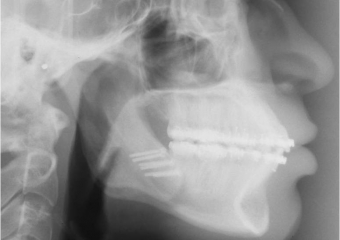

Telerradiografia após cirurgia